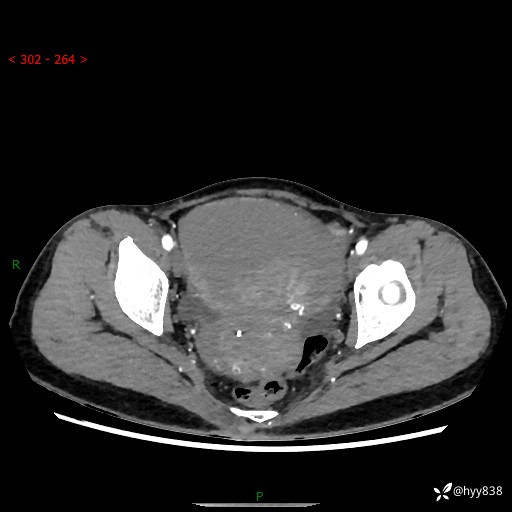

【患者信息】:女,50岁

【主诉】:外院超声发现腹盆肿块,为进一步诊治来我院,门诊已“盆腔肿块”收入院。

腹盆CT平扫+增强

【临床诊断】:盆腔肿瘤